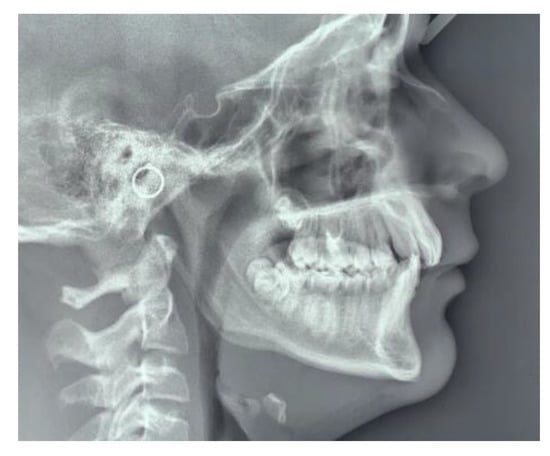

Lateral cephalometric radiographs were used to measure skeletal relationship angle (ANB) and evaluate PP (Figure 1), sella bridging (Figure 2) and atlas posterior arch deficiency (Figure 3).

The extent of PP osseous anomaly of the atlas vertebra was estimated following the classifications of Cederberg and Stubbs [14,15]: Grade 1—the absence of calcification, Grade 2—the presence of calcifications which extend for less than half the distance between the posterior segment of the upper articular process and the lateral and posterior segment of the superior portion of the posterior atlas arch, Grade 3—calcifications which extend for more than half the distance between the posterior portion of the superior articular process and the posterolateral portion of the upper margin of the posterior arch of the atlas but which do not form a complete ring, Grade 4—calcifications forming a complete bone ring.

Figure 1. Ponticulus posticus (PP) full ring.